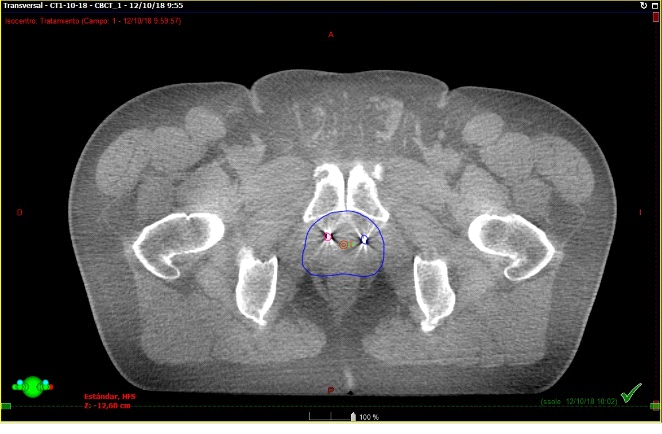

Se presentan figuras de un caso clínico de nuestro centro. Paciente de 57 años, APE: 6.5, Biopsia Gleason 7 (3+4) 2/6 sextantes. Etapificación (-), Rechaza cirugía.

Fig. 8. Paciente en tratamiento. Esta imagen corresponde el conbeamCT que se realiza en cada sesión de tratamiento y se superpone con el TAC previo de simulación que tiene los contornos. El contorno azul fue realizado previamente en el TAC de simulación. Así sabemos que la dosis llegará sólo sobre ese sector.